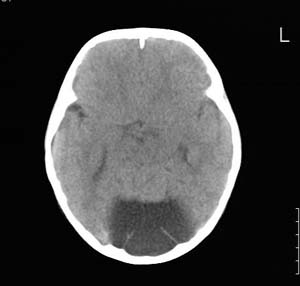

以下是引用lixi在2006-12-5 21:06:00的发言:[br]1、dandy-walker变异。2、胼胝体发育不良。

以下是引用zhuoshandiao在2006-12-5 21:41:00的发言:[br]胼胝体发育不良应该是肯定的。另外考虑dand-walker畸形。

以下是引用卜一在2006-12-5 22:30:00的发言:[br]支持考虑:1、dandy-walker变异。2、胼胝体发育不良